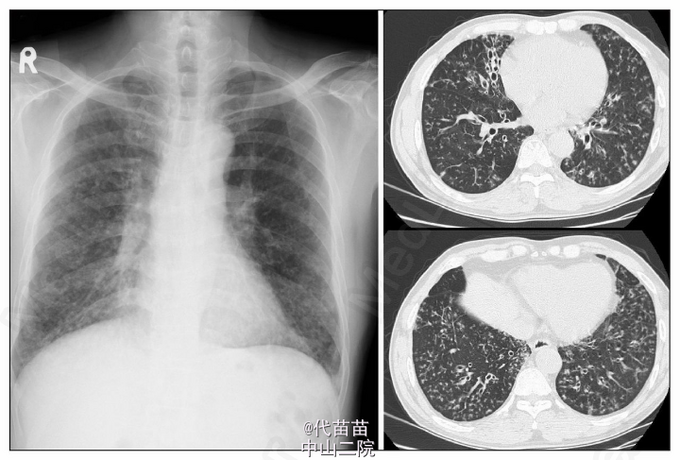

63岁男性,出现咳嗽伴大量脓痰和进行性劳力性气促,已持续10年。病史包括慢性鼻窦炎。听诊闻及干罗音和粗糙的肺泡音。实验室检查结果正常。胸透发现弥漫性网状阴影,CT扫描发现支气管扩张,小叶中心型结节和树芽状混浊。随后确诊为弥漫性细支气管炎。